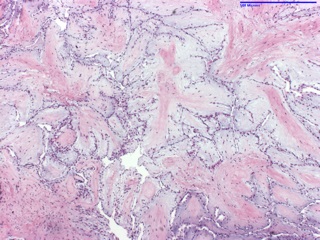

Papillary fibroelastoma is the most common valve tumor and is often discovered accidentally. When symptomatic, the most common presentation is stroke, followed by TIA and myocardial infarction. Grossly is classically described as “sea anemone”, with central stalk and fronds-like arms projecting outward, appearance that becomes more evident by placing the specimen in water.

Thrombi may occur on their surface and dislodged clots are responsible for embolic events. Most are smaller than 1cm but can be up to several cm large.

Histologically, they are composed primarily by collagen and elastin at the base with abundant mucopolysaccharide stroma, and outer endothelium expressing vimentin, factor VIII and CD34. The vasculature is minimal while myxomas (the main differential) are highly vascular lesions with typical “myxoma” cells and very rarely occur in heart valves.